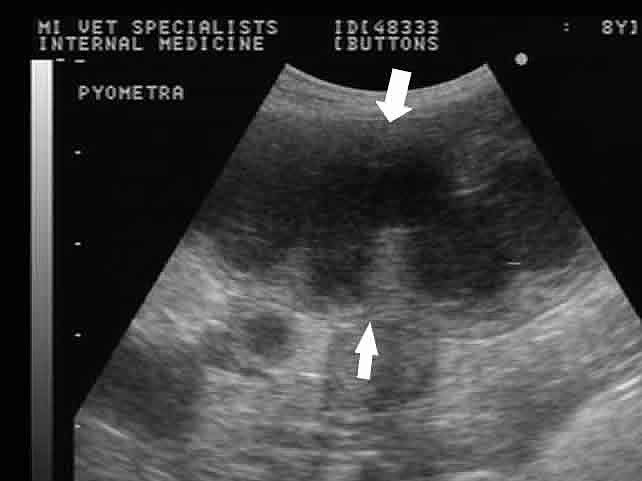

Как при других заболеваниях, исходом успешного лечения считается вовремя проведенная диагностика. Однако установить правильный диагноз на Пинап стадии развития болезни сложно, так как симптомы очень неоднозначны. Заметив ухудшение состояния здоровья у питомца, лучше незамедлительновызвать высококвалифицированную ветеринарную помощь на дом. Основным приемом Пинап пиометры считается обследование ультразвуковетеринарной клинике НЕОТЛОЖКАсделают УЗИ собаке, возьмут необходимые анализы и установят Пинап диагноз.